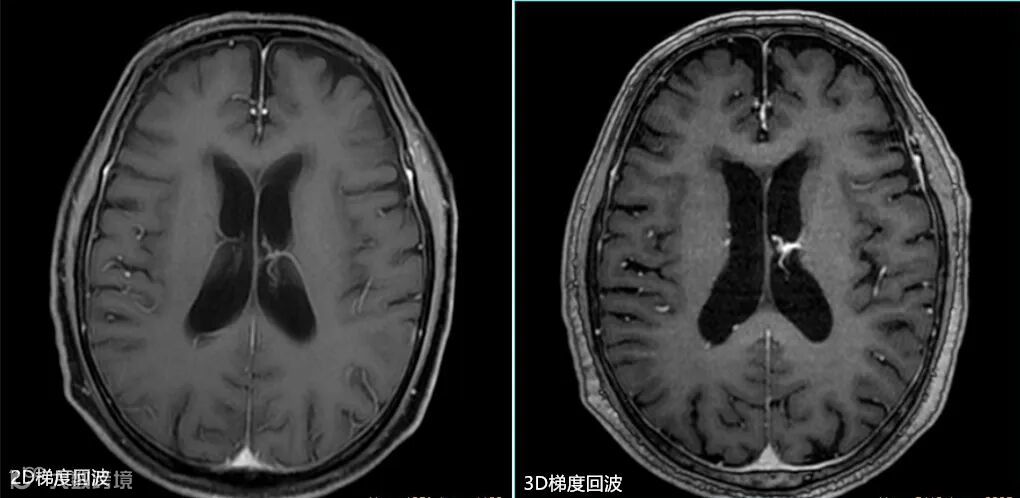

- 但该序列磁敏感伪影较重,图像灰白质对比也不及自旋回波序列,特别是采用压脂后其图像对比明显下降。如上图△,2D T1自旋回波序列与2D T1扰相梯度回波序列的比较。

该类序列成像时间较短,同时,加入了反转模块后的3D梯度回波序列较2D的梯度回波序列灰白质对比更好,在显示灰白质结构方面具有优势,其在头颅增强中的应用较为广泛。如上图△,2D T1扰相梯度回波序列与3D磁化准备梯度回波序列的比较。 -